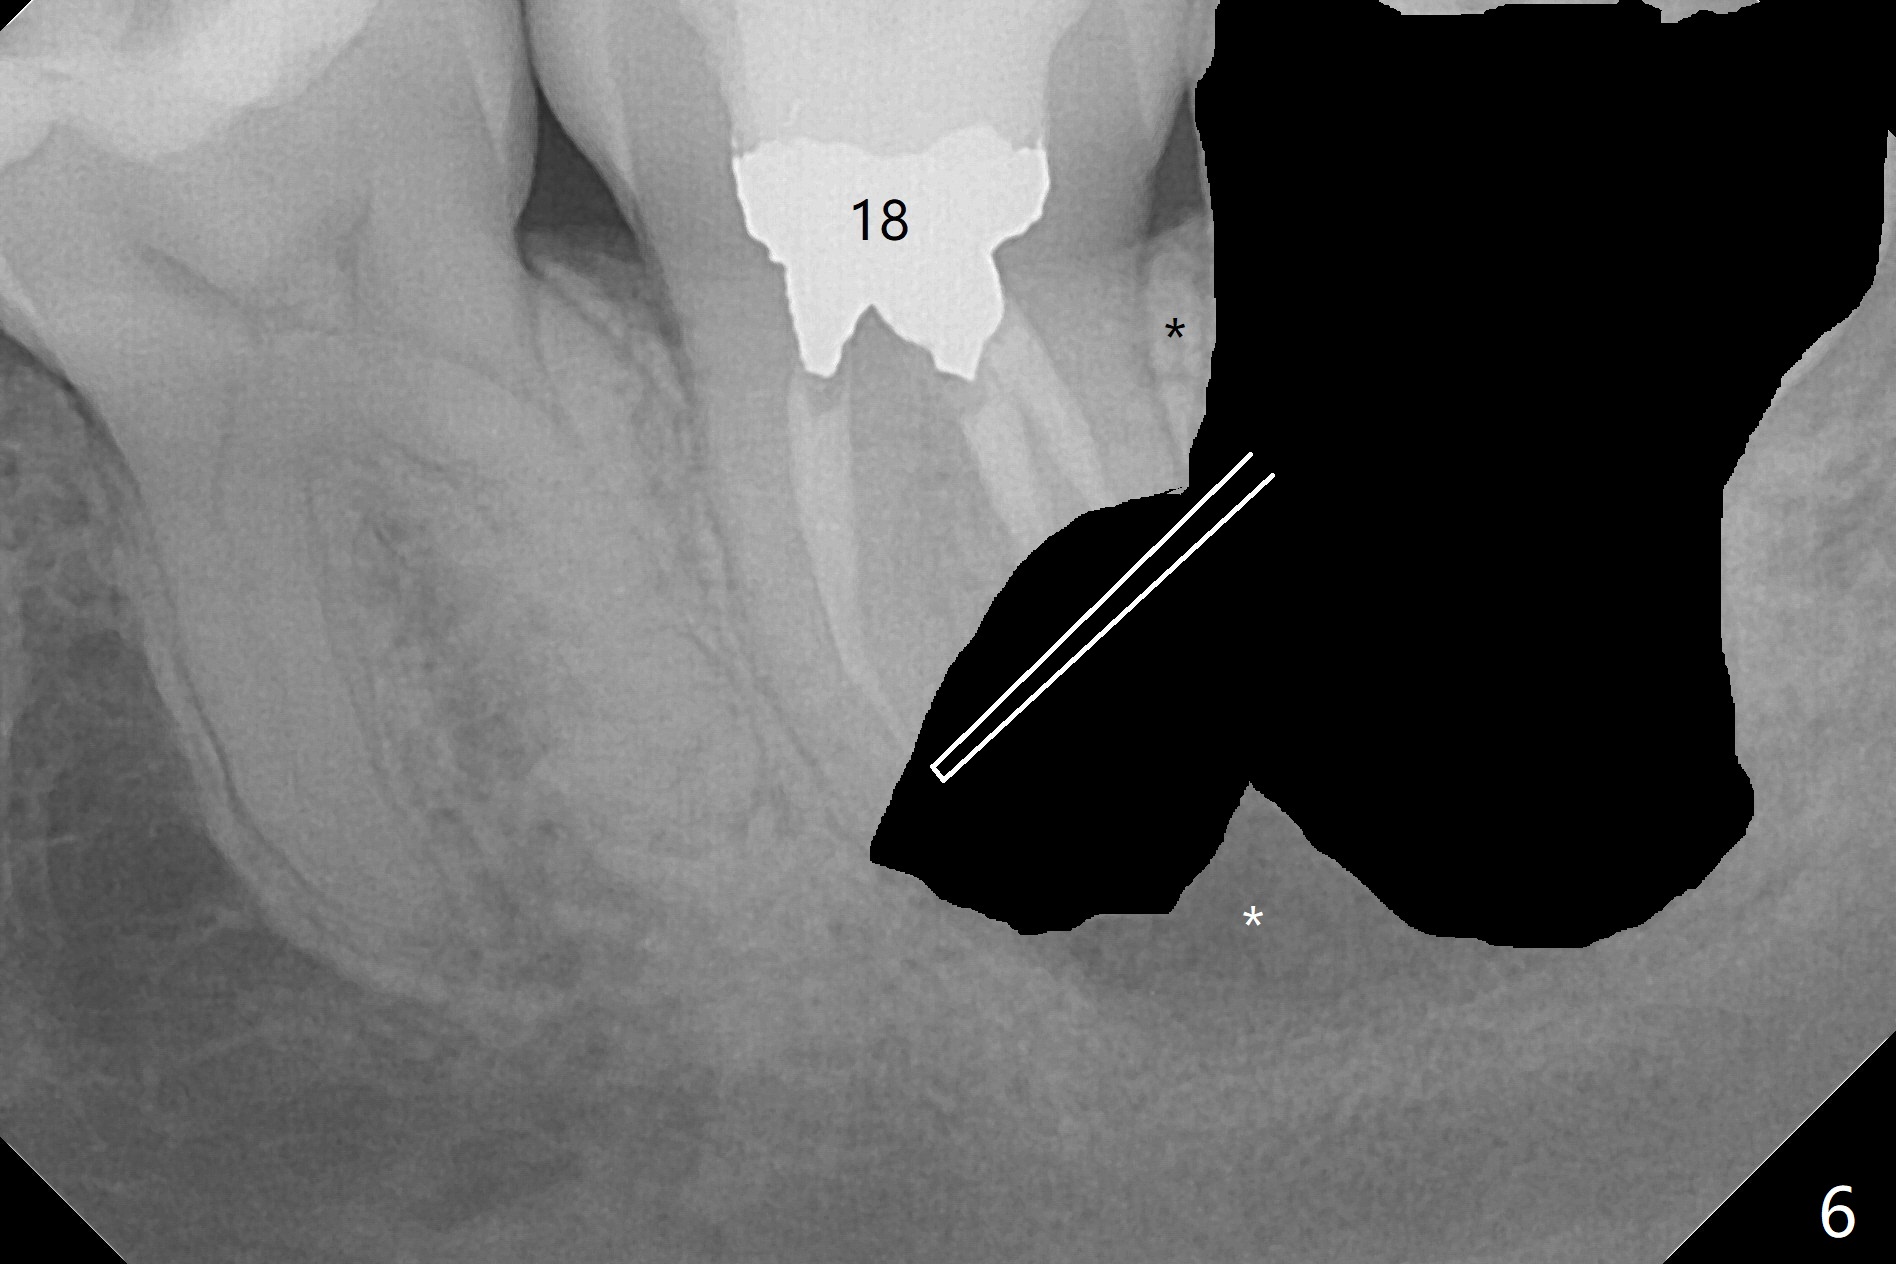

A 37-year-old woman requests extraction of the 3rd molars and orthodontic retreatment (Fig.1). Since the bone between #17 and 18 is thin and short (Fig.2 black *), bone graft is needed after #17 extraction. But the apical infection at #18 (Fig.2 white *) may affect graft survival. The patient agrees to have RCT retreatment done (Fig.3 white curved lines) before extraction (black area). The apical granulation tissue can be removed (Fig.4 red area) prior to bone graft (Augma). The latter will be also placed at #17 as a control. After endodontic consultation, the patient does not want RCT retreatment. She would like to have the 3rd molars extracted first and #18 removed if needed. After #17 extraction (Fig.5), apicoectomy will be performed at #18 (Fig.6 (white outline: surgical bur, use non-torque handpiece)). Following curettage of the apical lesion at #18 (Fig.7), bone graft will be placed (Fig.8 red circles). In fact the patient insists upon #1, 16, 17, and 32 extraction. After extraction, allograft (Fig.9 A (Ossogen, Mineralized Cort/Can (30%/70%), .25-1.0 mm) is placed in the mesioapical of the sockets of #17 and 32, while Osteogen Plug (O) and BioXclude in the distocoronal one (4-0 PGA suture). There is minimal bone between the 2nd and 3rd molars (black arrowheads). The allograft is intentionally pushed into #18 apical defect after enucleation (white arrowhead). The sockets are slightly open, although sutures are in place 2 weeks postop (Fig.10,11). It is unknown whether the bone graft is partially dislodged or not.